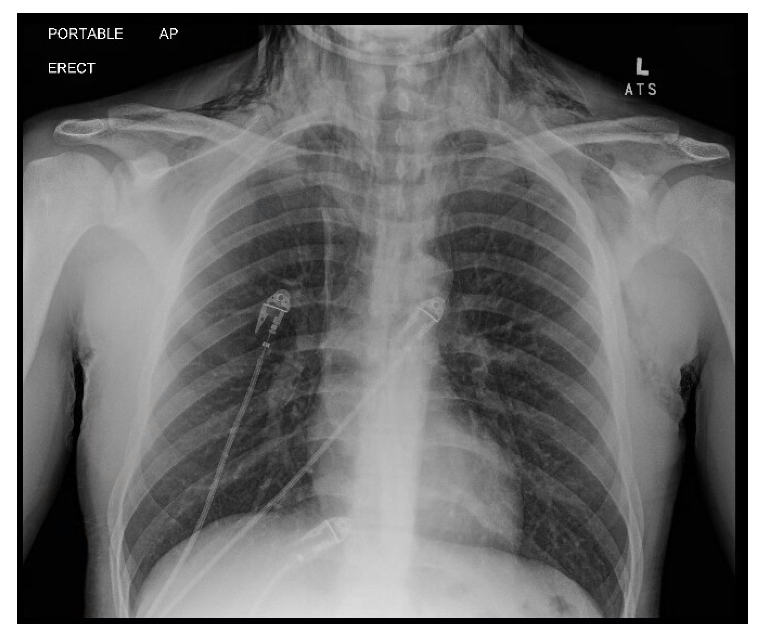

Figure 1: Chest X-Ray: Pneumomediastinum and subcutaneous emphysema in the supraclavicular region in the base of the neck and left hemithorax  |

Initial chest radiograph demonstrated pneumomediastinum and subcutaneous emphysema in the neck and upper thorax. A CT chest with oral contrast was obtained to evaluate for esophageal perforation, given the presence of pneumomediastinum and subcutaneous emphysema in the setting of repeated emesis. Imaging confirmed extensive pneumomediastinum and subcutaneous emphysema, but no contrast extravasation, no pneumothorax, and no radiologic evidence of esophageal rupture were identified. These findings effectively ruled out esophageal perforation, supporting a diagnosis of spontaneous pneumomediastinum secondary to barotrauma from forceful vomiting. Laboratory evaluation was notable for leukocytosis (WBC 16.2 × 10⁹/L), acute kidney injury (creatinine 2.31 mg/dL, which improved with IV fluid resuscitation), and a positive urine drug screen for THC. Arterial blood gas (ABG) revealed a mixed alkalosis: primary respiratory alkalosis with secondary metabolic alkalosis (pH 7.62, pCO₂ 27 mmHg, HCO₃⁻ 28 mmol/L).